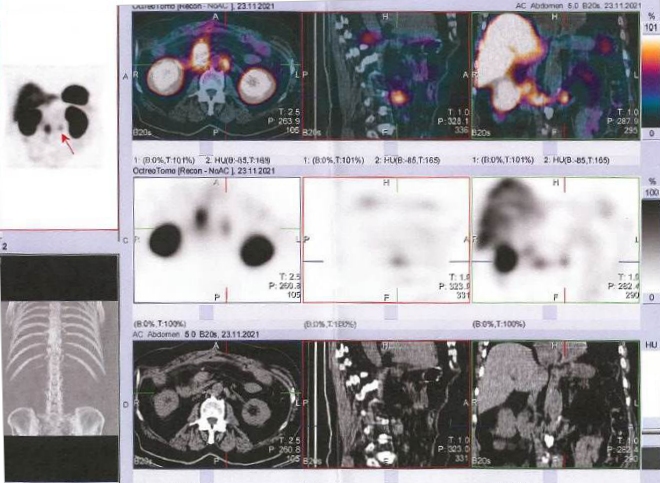

/ Obr. č. 3: Fúze SPECT/CT břicha a pánve 24 hod. po aplikaci OctreoScanu.

Popis: Prokazujeme dva okrsky patologicky zvýšené hustoty somatostatinových receptorů v paketu LU na mesenteriu vpravo ve výši L2 a v LU v retroperitoneu paraortálně vlevo ve stejné úrovni - svědčí nejspíše pro metastázy NET.